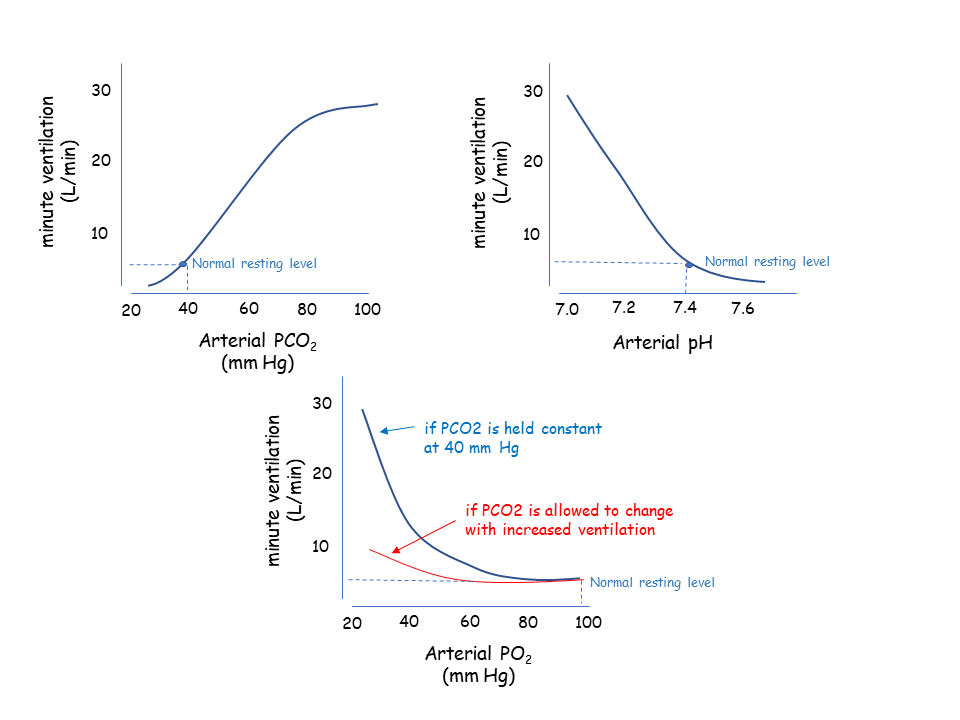

- Peak Expiratory Flow – this test can be done to measure the severity of airway obstruction.